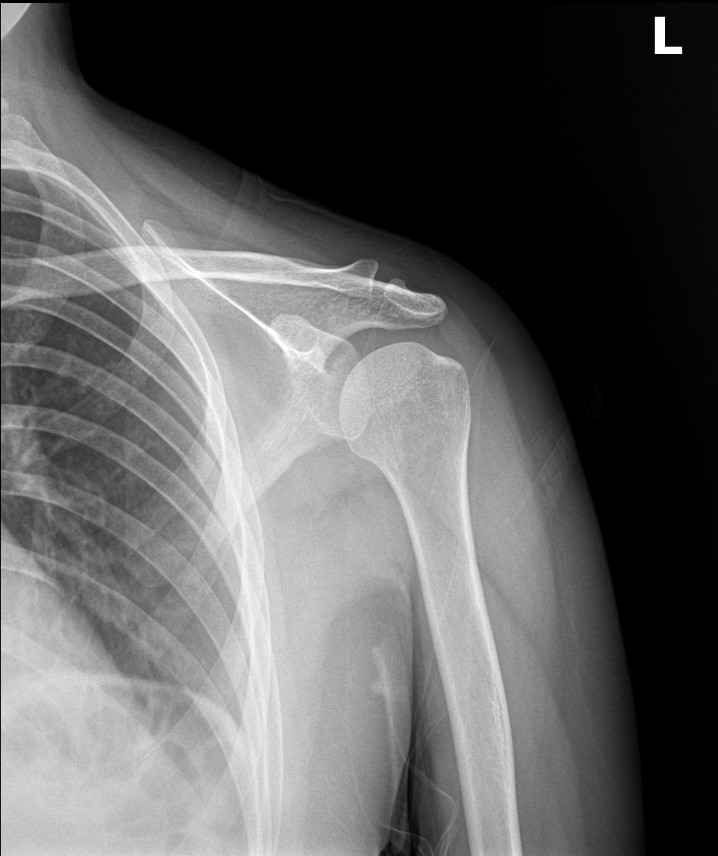

영상 검사를 다시 확인했습니다. 견봉뼈는 정상 범위였습니다.